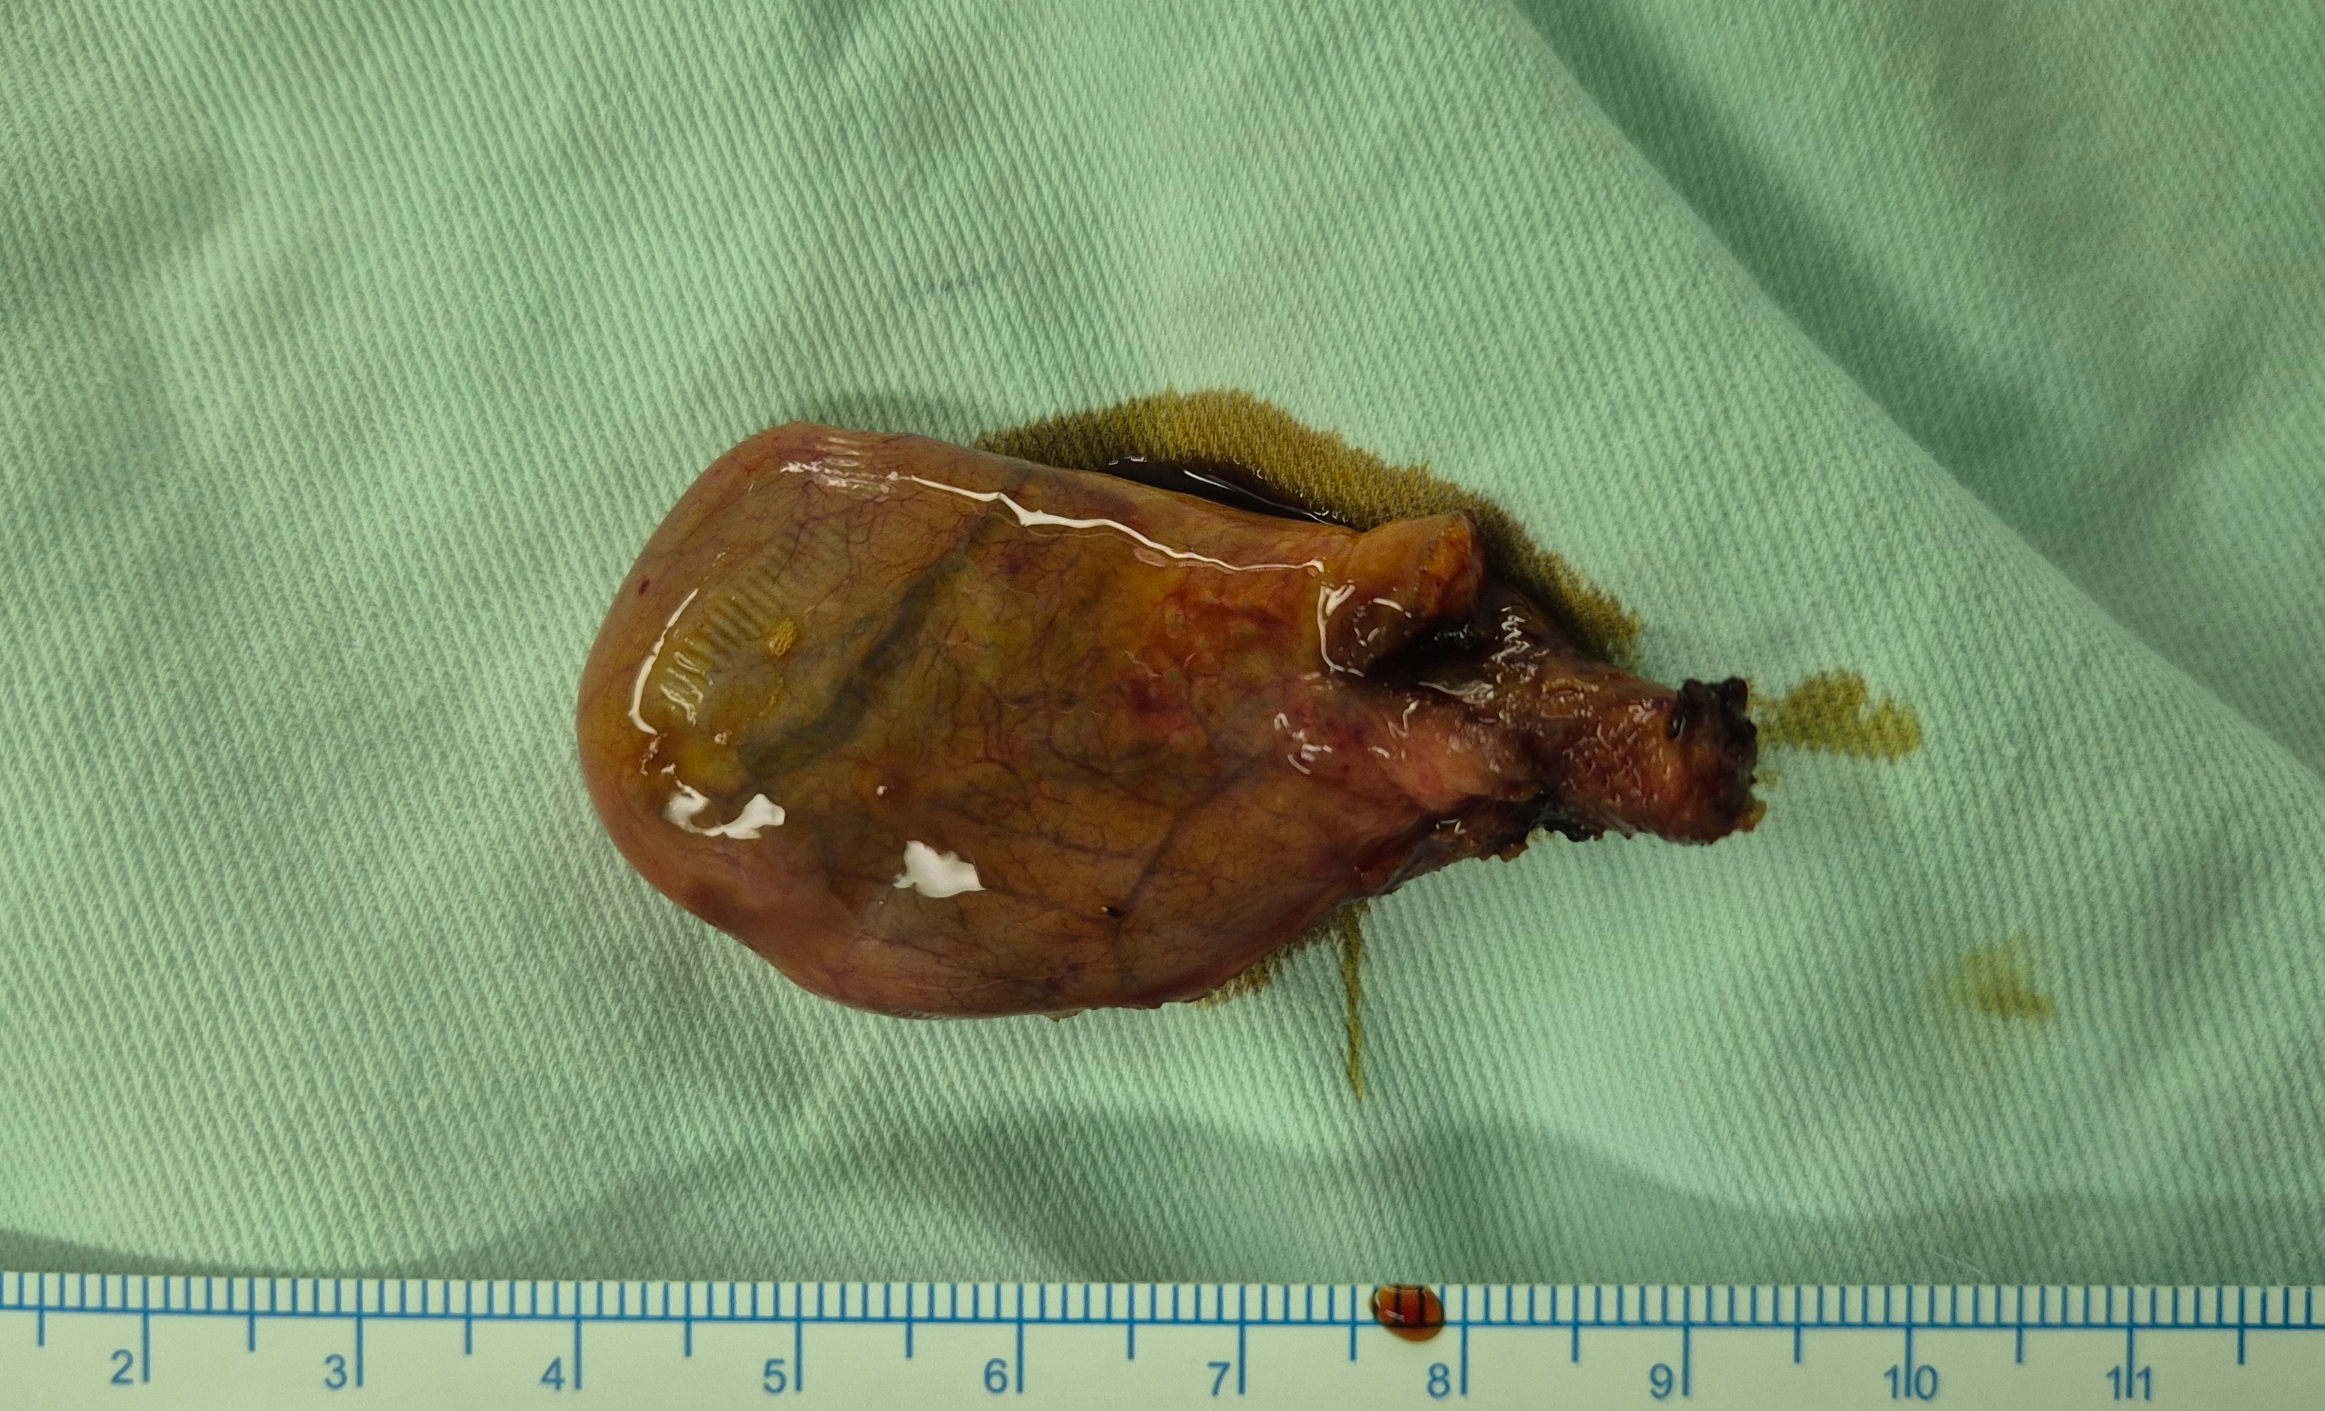

담낭용종 알고 계셨고 죄근 0.9cm으로 커져 수술위해 제 외래로 오셨던 분입니다.

로봇(다빈치sp) 단일공 담낭절제술을 시행했습니다.

수술은 35분 걸렸습니다.